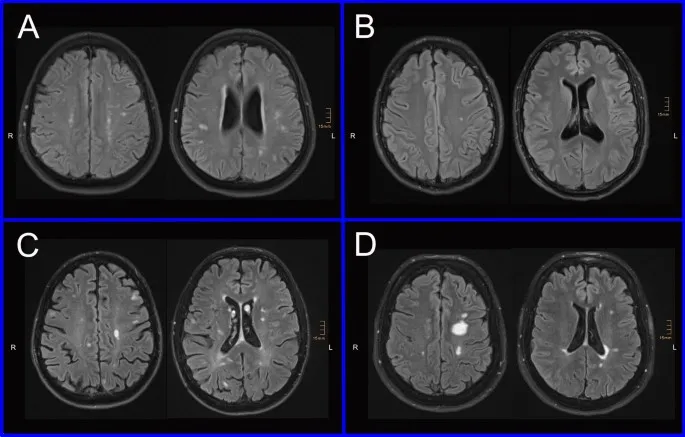

- Brain MRI: DTI changes monitoring white matter in MPS disorders